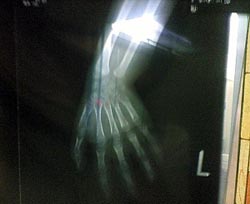

それに手首の骨のレントゲン・・・骨年齢を調べるそうです。

レントゲン